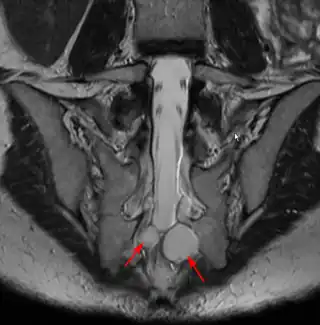

![]() IRM mostrando un quiste de Tarlov. | ||

Los quistes de Tarlov (QT), también denominados quistes perineurales, periradiculares o quistes aracnoideos extradurales, son pequeñas masas que se forman a expensas de las dos capas más internas de las meninges, la piamadre y el aracnoides. Los quistes, que contienen líquido cefalorraquídeo (LCR), presentan un pedículo, a través del cual se comunican con el espacio subaracnoideo espinal, y se sitúan alrededor de los nervios de la zona sacra y lumbar, y suelen diagnosticarse de manera incidental en el transcurso de una Resonancia Magnética (RMN). Por lo tanto, si bien los QTs son quistes perinerviosos, corresponden a una dilatación de la dura madre y son pues una enfermedad de la dura madre y no de las raíces nerviosas, que son afectadas de forma secundaria (compresión) por estos quistes.

Ubicación y estructura

En cuanto a su ubicación, los QT’s se encuentran habitualmente en la zona sacra alrededor de las raíces nerviosas posteriores, los quistes anteriores son escasos. Los QT’s múltiples no son raros. Aunque un quiste de gran tamaño puede causar síntomas por presión de una estructura o nervio adyacente, los síntomas pueden también ser causados por la presión que ejerce el LCR en los nervios situados en el interior del quiste o en su pared (4). Por lo tanto quistes menores incluso de 1 cm pueden ser altamente sintomáticos.